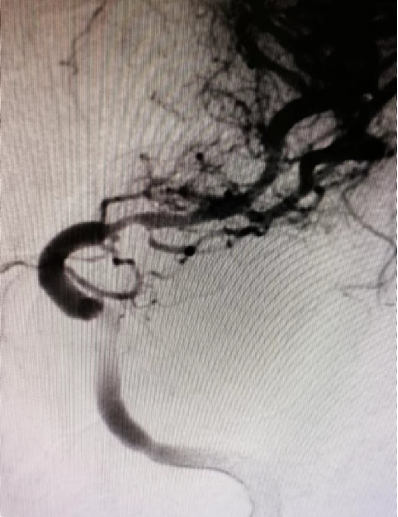

治疗中影像

在微导丝辅助下将赛诺神畅颅内药物洗脱支架NOVA DES®2.25*10mm于大脑中动脉狭窄处行支架成形术。

导丝怎么扩【载药时代 球扩天下】NOVA DES®颅内药物洗脱支架在大脑中动脉重度狭窄中的应用两例!_https://www.jmylbn.com_新闻资讯_第18张

导丝怎么扩【载药时代 球扩天下】NOVA DES®颅内药物洗脱支架在大脑中动脉重度狭窄中的应用两例!_https://www.jmylbn.com_新闻资讯_第19张

球扩后狭窄解除。

导丝怎么扩【载药时代 球扩天下】NOVA DES®颅内药物洗脱支架在大脑中动脉重度狭窄中的应用两例!_https://www.jmylbn.com_新闻资讯_第20张

导丝怎么扩【载药时代 球扩天下】NOVA DES®颅内药物洗脱支架在大脑中动脉重度狭窄中的应用两例!_https://www.jmylbn.com_新闻资讯_第21张